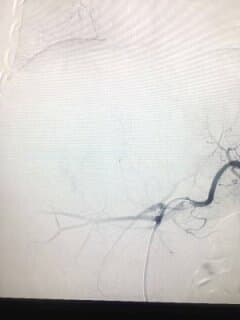

介入硬化治疗淋巴管畸形是用细针经皮穿刺淋巴囊,抽出淋巴液,再注入硬化剂,硬化剂破坏囊壁细胞,导致淋巴管畸形囊腔纤维化闭塞,消失!

因为注入的硬化剂是液体,会在淋巴管畸形囊内流动弥散,所以治疗无“死角”,治疗后不复发!